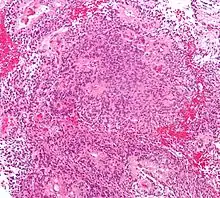

| Micrograph of an ependymoma. H&E stain. | |

Ependymomas are composed of cells with regular, round to oval nuclei. There is a variably dense fibrillary background. Tumor cells may form gland-like round or elongated structures that resemble the embryologic ependymal canal, with long, delicate processes extending into the lumen; more frequently present are perivascular pseudorosettes in which tumor cells are arranged around vessels with an intervening zone consisting of thin ependymal processes directed toward the wall of the vessel.[4]